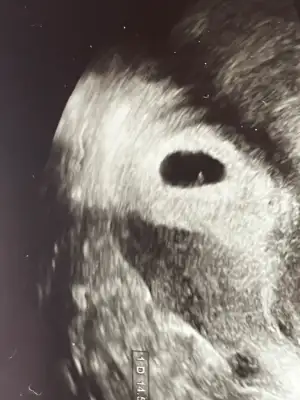

Hangisi bebek hangisi yolk sac hiç bişey anlamıyorum şu ultrasonlardan ya. Gerçi benek gözüküyor mu onuda bilmiyorum. 6+4 haftaya kalp atışı için çağırdı acaba duyulması gerekmezmiydi bugün moralim bozuldu

Eklentiler

• IMG_1655.webp

IMG_1655.webp

26,5 KB · Görüntüleme: 44

• IMG_1656.webp

IMG_1656.webp

32,2 KB · Görüntüleme: 42

Bence ultrason cihazına göre değişiyor ya 2 gün önce başka sebepten aynı hastane farklı doktora gittim bebeğide yolk sac ta gördü ultrasonda. Ama bugün kendi doktorum yolk sac gözüküyor diye not aldı sadece. Sonra baktım ultrason markaları farklı ben onla alakalı olabileceğini düşünüyorum